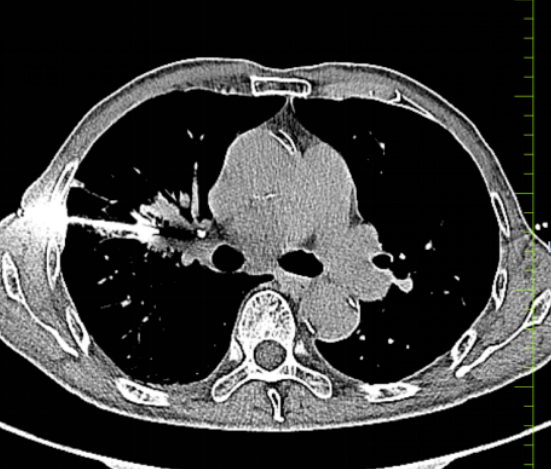

此次接受穿刺的患者已是高龄,检查后发现,患者右肺存在明确占位性病灶,且病灶周边血管分支异常密集,属于典型的富血供病灶。这一特殊病灶情况,给穿刺操作带来极大隐患:穿刺针尖只要出现微小偏差,就极易刺破周边血管,引发大出血、血气胸等严重并发症,甚至直接危及患者生命,堪称临床穿刺的“高危禁区”。

术前,团队借助增强CT三维重建,精细分析病灶与周围血管、胸膜的关系,规划最优穿刺路径,并设定进针角度、深度与速度。针对患者高龄易紧张的特点,医护人员还进行一对一呼吸训练,帮助其平稳配合。

手术当日,在CT精准定位下,穿刺针一次性抵达病灶核心,成功获取足量病理组织,术中无渗血、无血管损伤。术后复查CT显示无出血、气胸等并发症,患者全程清醒,生命体征平稳。

此次手术的成功,体现了医院在复杂高危肺病变微创诊疗领域的技术实力。CT引导下经皮肺穿刺活检是肺部占位诊断的“金标准”,通过术前精准评估、术中精细操作、术后精心护理,不仅实现了安全穿刺、零严重并发症,更为后续明确病理分型及制定靶向、保守等个性化治疗方案提供了关键依据。